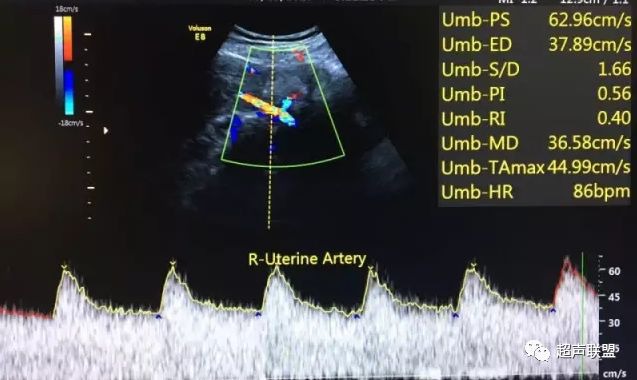

图1 正常脐动脉血流频谱